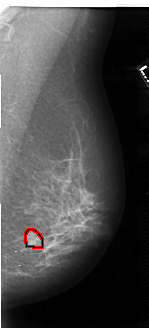

FILE: A_1050_1.RIGHT_MLO.OVERLAY

TOTAL_ABNORMALITIES 1

ABNORMALITY 1

LESION_TYPE MASS SHAPE LOBULATED MARGINS ILL_DEFINED

ASSESSMENT 4

SUBTLETY 4

PATHOLOGY MALIGNANT

TOTAL_OUTLINES 1

BOUNDARY